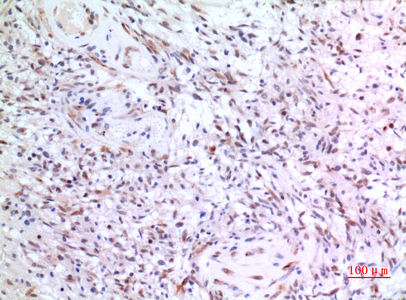

Immunohistochemistry analysis of paraffin-embedded Human brain using ZNF307 antibody.High-pressure and temperature Sodium Citrate pH 6.0 was used for antigen retrieval. |